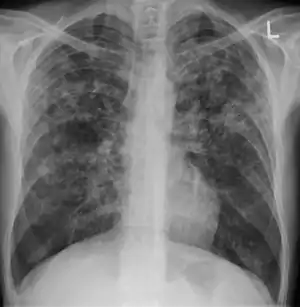

A case of miliary tuberculosis in an 82-year-old woman:

X-ray, 22 days after onset, showing extensive bilateral reticulo-nodular infiltrates